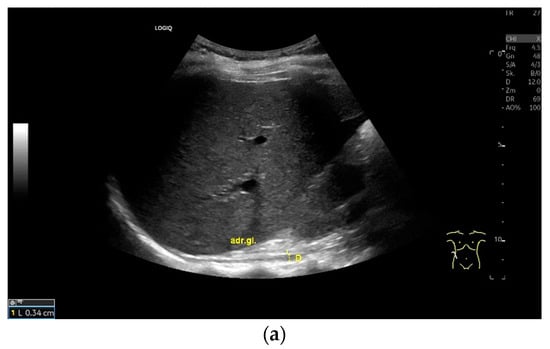

Subxiphoid: The diaphragm can be positioned directly subxiphoidally with a slightly sagittal transducer position on both sides next to the attachment to the sternum. The diaphragm limb can be demarcated to the right in the epigastrium in cross section between the aorta and the inferior vena cava. However, this is primarily of differential diagnostic importance, e.g., in relation to lymphomas, not for the actual assessment of the diaphragm (Figure 6).